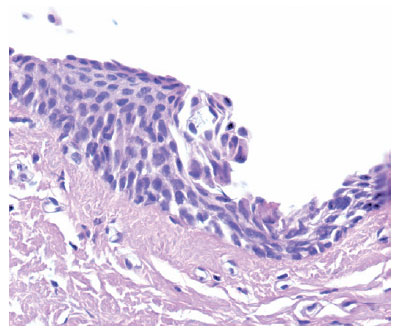

We used the following histopathological criteria to classify the OSSN lesions (Figure 1): Conjunctival intraepithelial neoplasia (CIN) grade I (mild dysplasia circumscribed to the basal third of the conjunctival-corneal epithelium), CIN grade II (moderate dysplasia restricted to the basal two-thirds of the conjunctival-corneal epithelium), CIN grade III/SCC in situ (severe dysplasia embracing the whole thickness of the conjunctival-corneal epithelium)(6).

We collected 177 samples from 172 patients (Figure 2) and confirmed clinical diagnoses of pterygium in all of them. Most samples (66.25%; n=114) were from women, and 35.46% (n=61) were from men. Their average age was 52.06 years (ranging from 25 to 77 years). We found 88.71% (n=157) of the samples had pterygium diagnoses by histopathology, whereas 11.29% (n=20) had histopathological diagnoses of OSSN (Table 1), and from this group, 19 of them (10.73%) with some degree of CIN. The histological reports included six (3.38%) biopsy samples with CIN I (Figure 3), nine (5.08%) with CIN II (Figure 4), and four (2.25%) with CIN III (Figure 5). One biopsy sample (0.56%) showed features of a poorly differentiated (Figure 6) keratinizing and infiltrating epidermoid carcinoma. We found no significant correlation between the presence of OSSN and any of the variables tested.